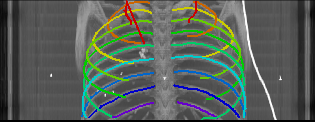

As can be seen from Table 2, we obtain overall good performance for the overall rib detection captured for example with an mean Dice of 0.84. Let us remark that for thin objects, such as the dilated rib centerlines, the Dice score constitutes a rather sensitive measure. The results indicate that detecting the first and twelfth rib pairs is more difficult for our network. While extraction of the first rib is more challenging due to, e.g., higher noise in the upper thorax or other bony structures in close vicinity (clavicle, shoulder blades, vertebrae), the twelfth rib can be extremely short and is easily confused by the neighboring ribs. For further illustration, Figure 4 shows the results on selected representative cases. Generally, the ribs are well detected without major false responses in other structures - despite all the different challenges present in the data. The color coding highlighting of the multi-label detection reveals that first and twelfth are mostly correctly detected. In few cases the network wrongly generated strong responses of the classes first rib or last rib for voxels belonging to the second or eleventh rib pair.

Refer to caption

Figure 4: Maximum intensity projections (MIP) of selected CT volumes overlaid with the multi-label output of the neural network (green: first rib; red: intermediate rib; blue: twelfth rib). The selected case above display common difficulties which are inherent in the data set, such as pads (a) or cables (b), internal devices such as pacemakers (c), stents (d), spinal (e) and femural/humeral implants (f), injected contrast agents (g), patient shape variations such as scoliosis (h), limited field of views (FOVs), i.e. partly missing first (i) or twelfth rib (j).